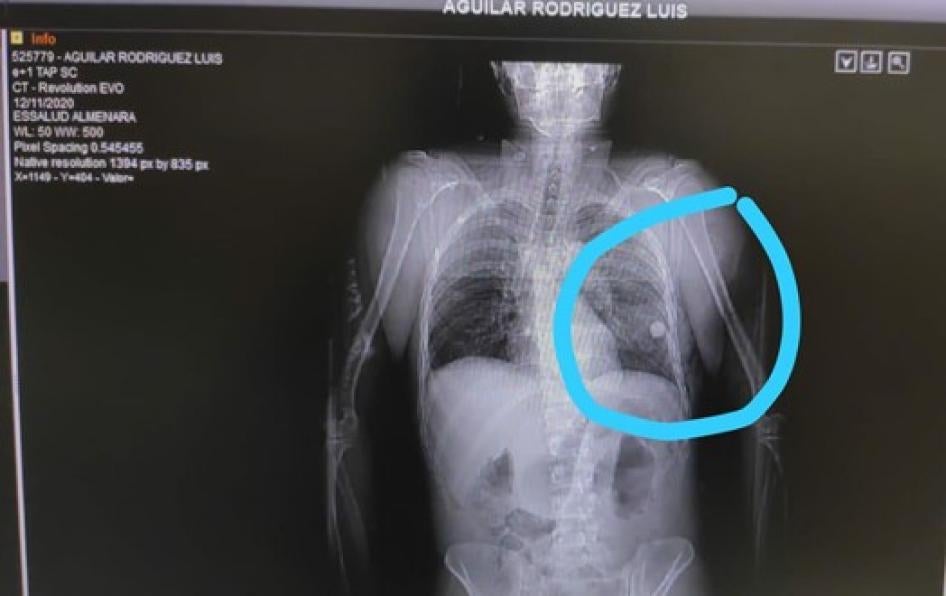

• Two protestors found Luis Aguilar Rodríguez, 26, bleeding from the chest on Abancay Avenue on November 12 and took him to a hospital, his mother said. After surgery, doctors told her that the object that had hit his chest, damaging his lungs, was a glass marble, which they removed. Aguilar Rodríguez left the hospital on November 30.

X-ray showing a marble lodged in Luis Aguilar Rodriguez’s lung. Photo courtesy of Luis Aguilar Rodriguez’s family.